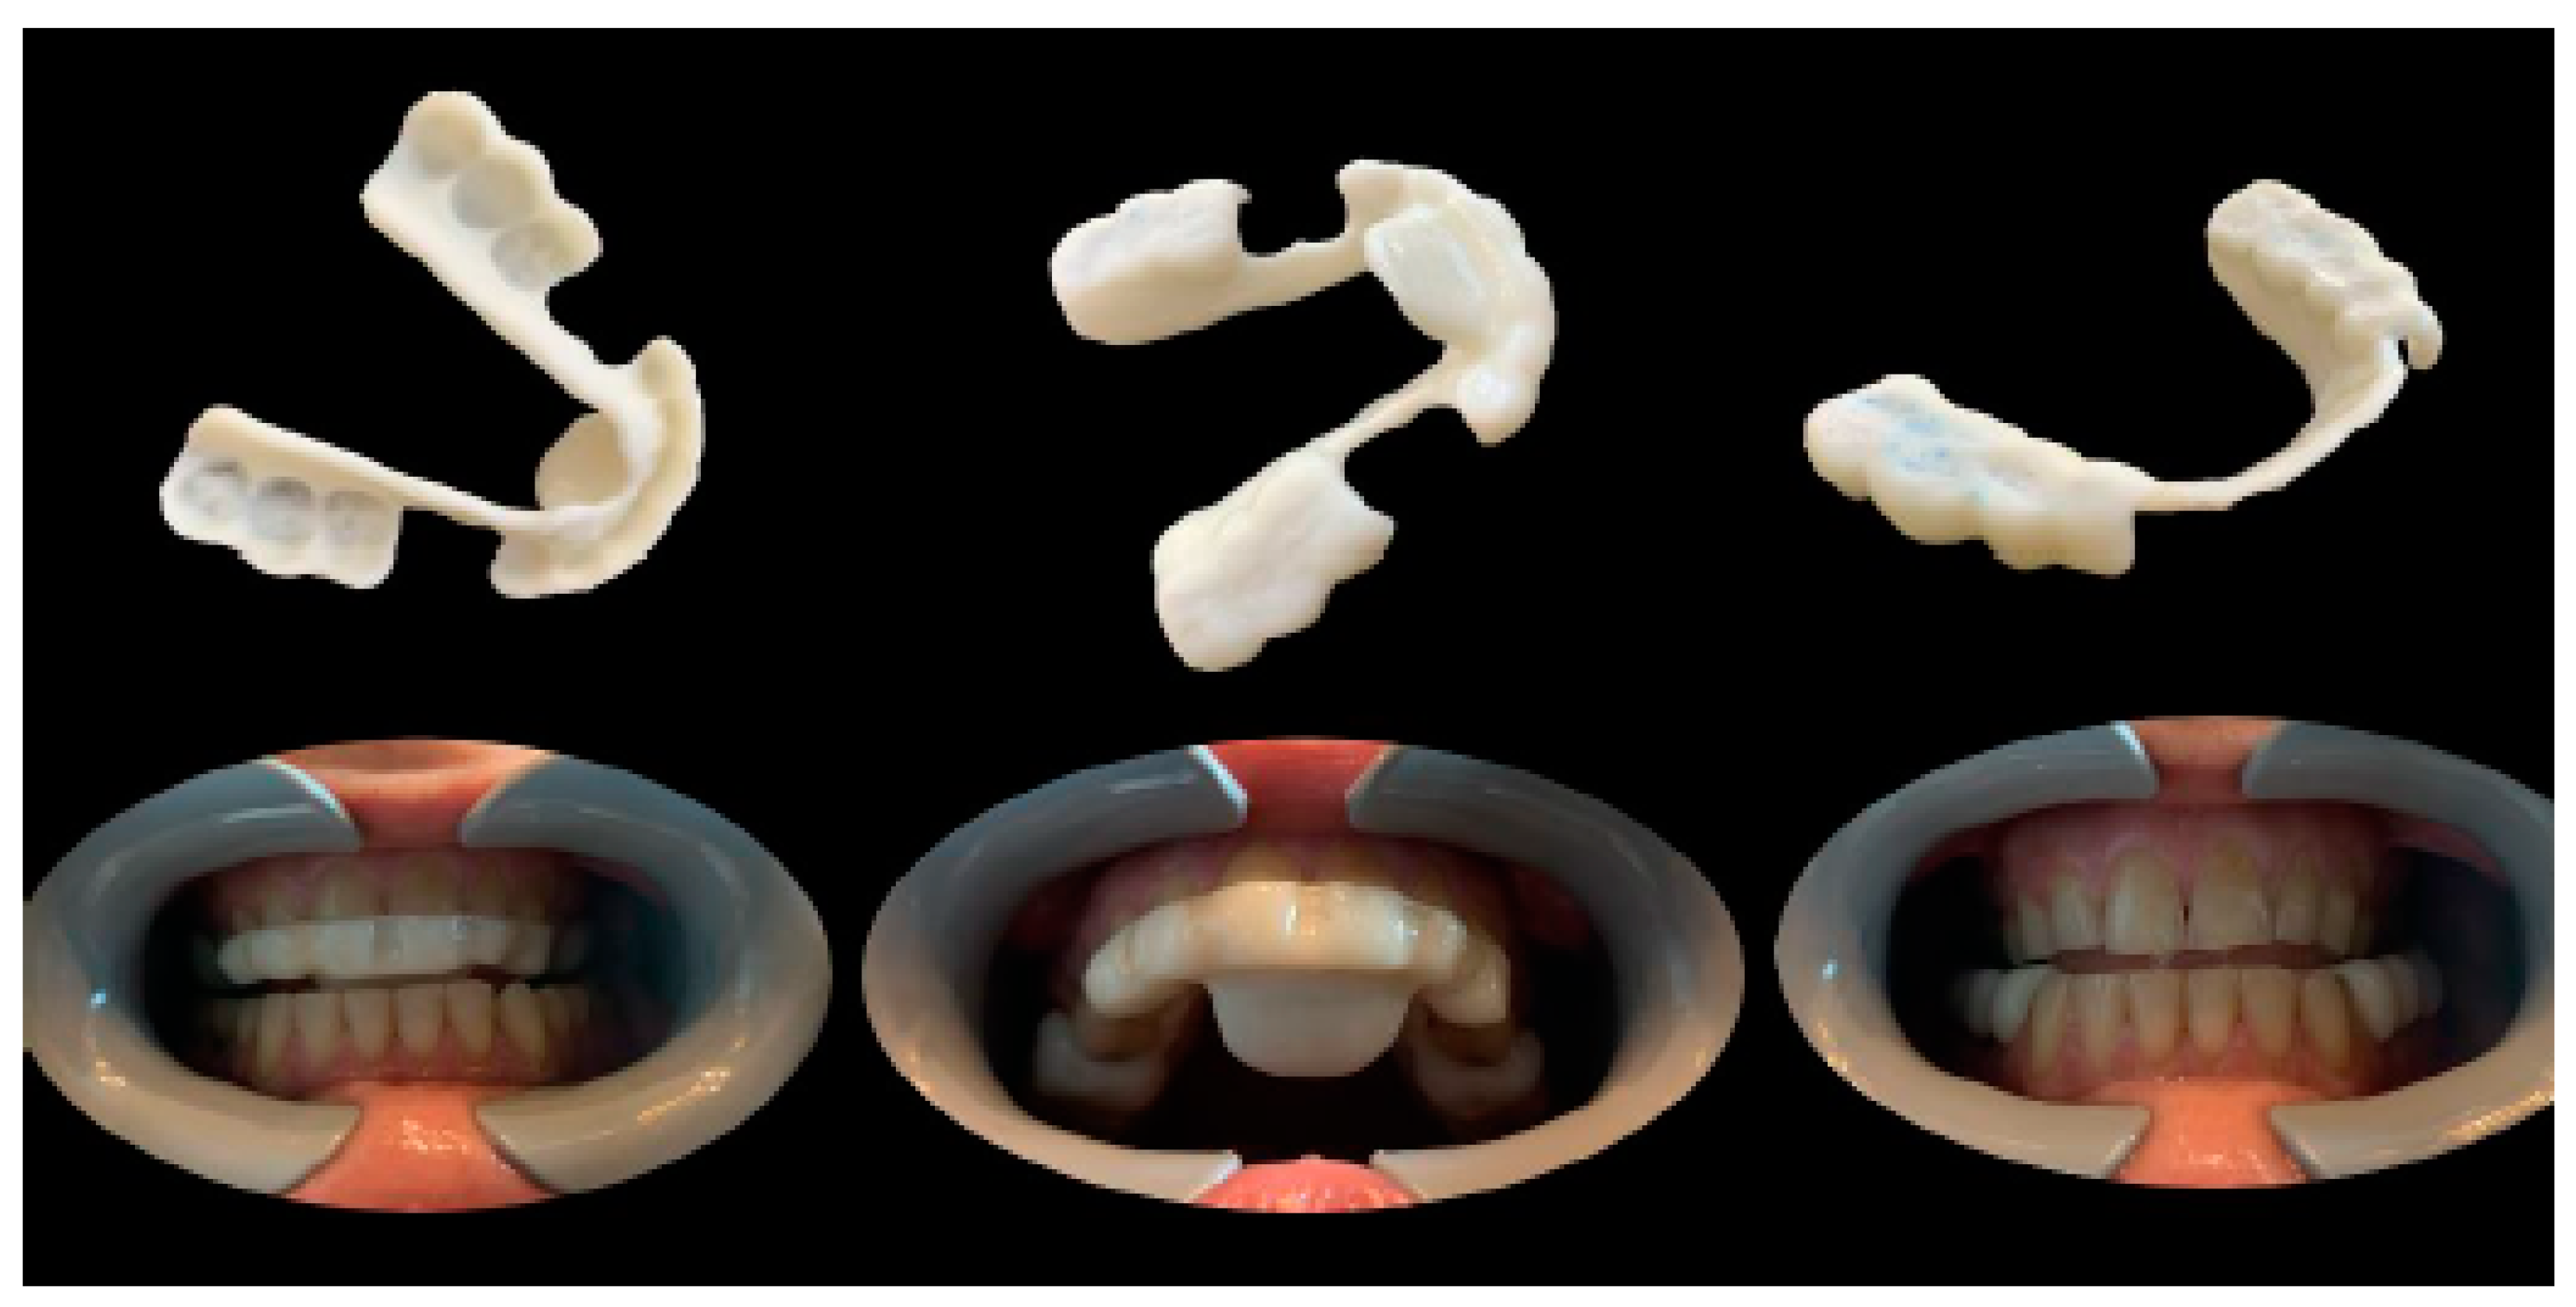

The position was planned to achieve an increase of intra-articular space and maintain a straight open tracing. Therefore, the position was recorded, and all the acquired data were digitally shared with the dental laboratory. In the present case, the lower occlusal device was digitally designed and printed (with the same procedure as the previous case reported), while the upper device was produced using a traditional method (Figure 23).

Figure 23. (a) Habitual occlusion; (b) upper device to be used during the night; and (c) lower device to be used during the day.